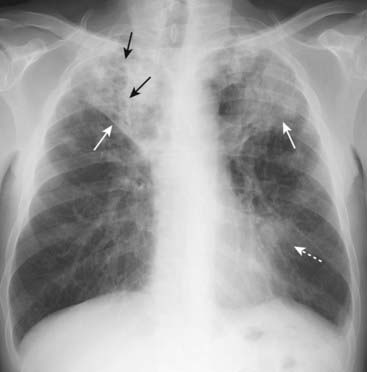

Figure 7-4 Staphylococcal bronchopneumonia.

Multiple irregularly marginated patches of airspace disease are present in both lungs (solid white arrows). This is a characteristic distribution and appearance of bronchopneumonia. The disease is spread centrifugally via the tracheobronchial tree to many foci in the lung at the same time so it frequently involves several segments. Because lung segments are not bound by fissures, the margins of segmental pneumonias tend to be fluffy and indistinct. No air bronchograms are present because inflammatory exudate fills the bronchi as well as the airspaces around them.